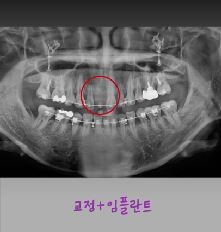

제목 교정중 임플란트는 언제 심을까요?

* 교정 중, 임플란트는 언제 심을까요?  *

교정 중 임플란트 타이밍은 결과를 좌우하는 중요한 포인트입니다.

✔ 대부분은 교정이 어느 정도 진행된 후

→ 공간 정리 & 치아 위치가 안정된 뒤 식립

✔ 경우에 따라 교정 중 식립도 가능

→ 교정용 기준점(앵커) 역할로 활용하기도 함

✔ 무조건 먼저 심는 건 위험

→ 치아 이동 계획이 바뀌면

임플란트 위치 수정  불가